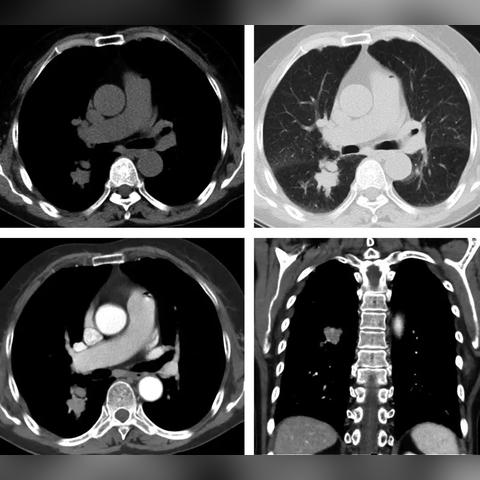

目前,基因检测和影像学检查是诊断结节性硬化症的主要手段,随着技术的发展,非侵入性的影像学检查如MRI和PET在诊断中的应用越来越广泛,生物标志物的研究也在不断深入,有助于早期诊断和病情监测。